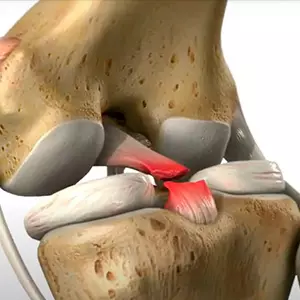

Tratamiento menisco rasgado

El tratamiento depende del tipo de lesión meniscal de la rodilla. Algunos se pueden tratar de forma conservadora, con reposo, hielo y medicamentos.

Reconstrucción del ligamento de la rodilla

Los ligamentos de la rodilla se pueden reparar quirúrgicamente mediante el uso de un pedazo de tendón sano del propio cuerpo del paciente o de un donante.